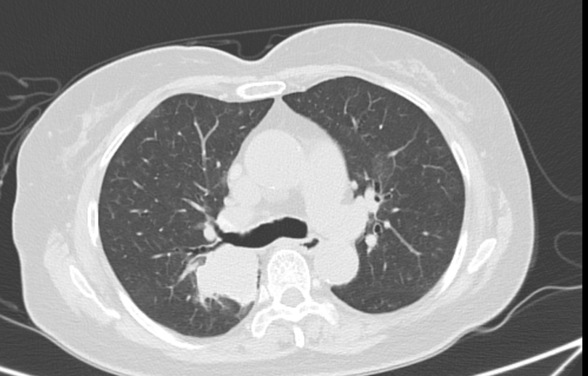

病例二:肺癌

患者,女,70岁,2021年10月发现肺占位,先在我市某医院行支气管镜检查,无阳性结果,后去天津某医院行CT引导下经皮肺穿刺活检,结果未找到恶性肿瘤细胞。后期定期随访,1年后病灶较前略有增大,遂来我院进一步诊治。后行超声引导下行经支气管针吸活检(EBUS-TBNA),明确诊断为肺腺癌。